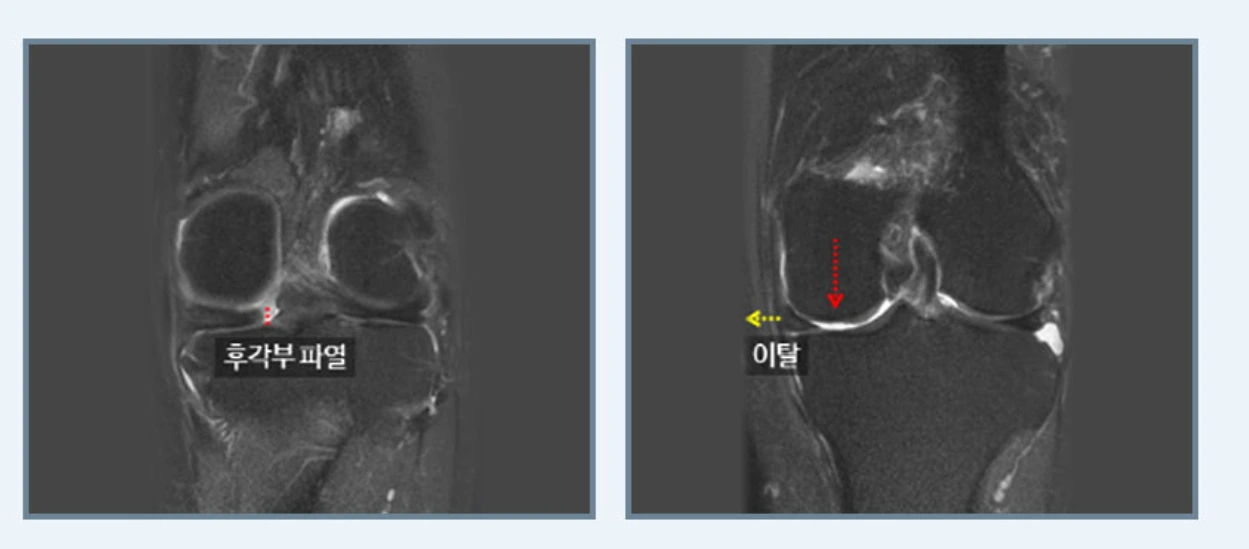

다음 연골판 봉합술은 연골판의 기능을 보존하기 위해 후각부의 파열을 봉합하는 것으로 체중을 가하거나 심한 운동을 할 경우에 재발할 수 있다는 단점이 있어 면밀한 검사가 필수입니다.

연골판봉학술.PNG

마지막 연골판 이식술은 파열된 반월상연골을 대신할 연골판을 이식하는 방법이지요.

연골판이식술.PNG